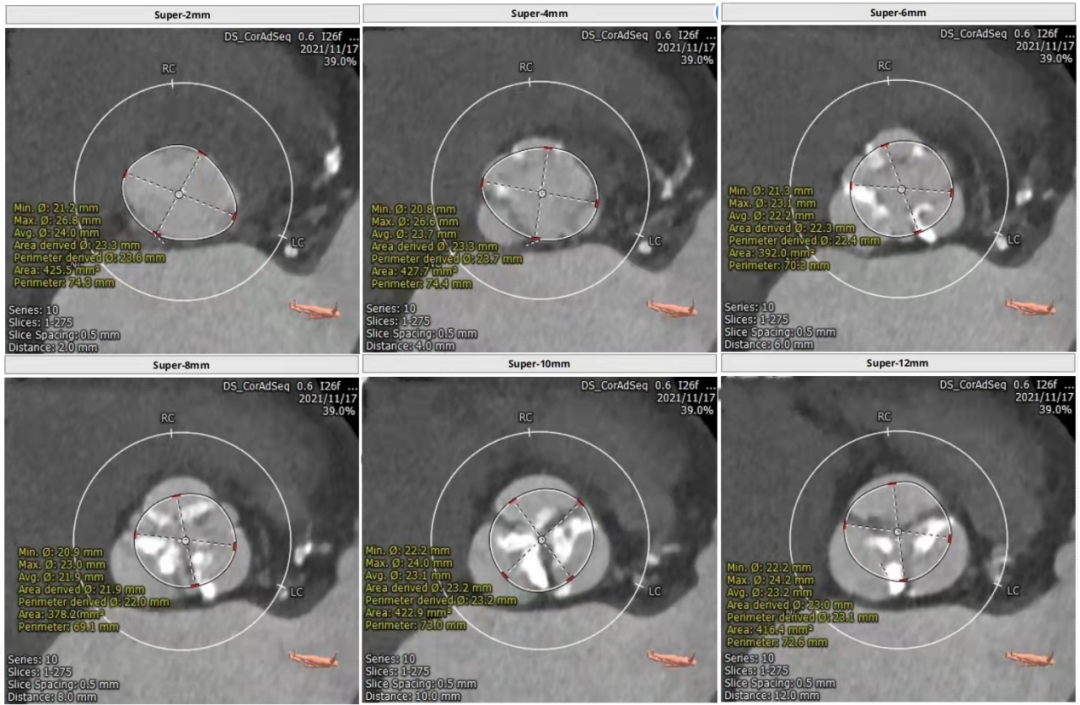

主动脉瓣CT评估

三叶瓣,瓣环径24mm,瓣环长短径分别为27.3*20.4mm,周长为75.5mm,面积为436.8mm²。左室流出道25.7mm,法式窦27.2mm*30.6mm*30.6mm,左冠高度19.3mm,右冠高度16.7mm,窦管交界 25.9mm,升主动脉直径29mm。

瓣上多平面测量